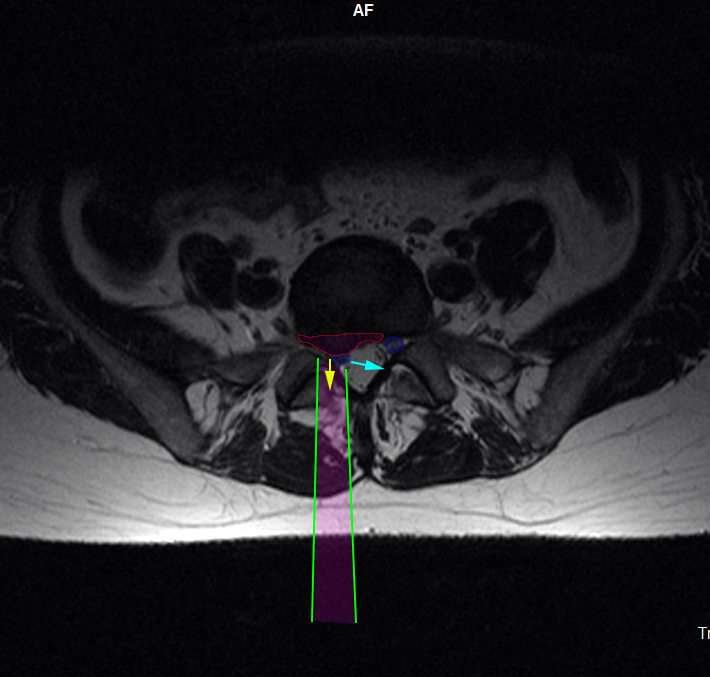

LumbarDiscectomy